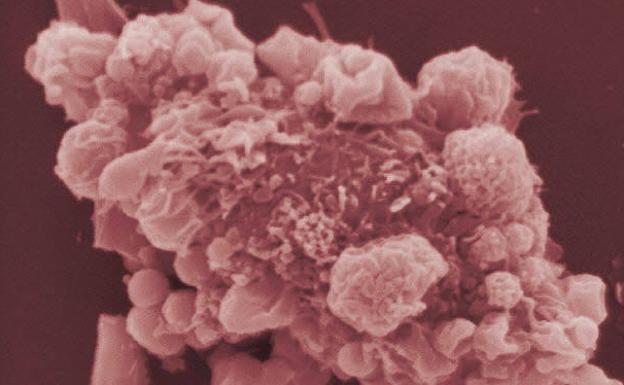

El cáncer le cuesta a los españoles 19.300 millones de euros al año

Reducir al mínimo tabaco, alcohol y obesidad y extender la detección precoz evitaría 55.000 muertes cada año y rebajaría a casi la mitad la factura de esta patología